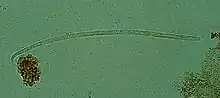

| Onchocerca volvulus, the causative agent of river blindness | |